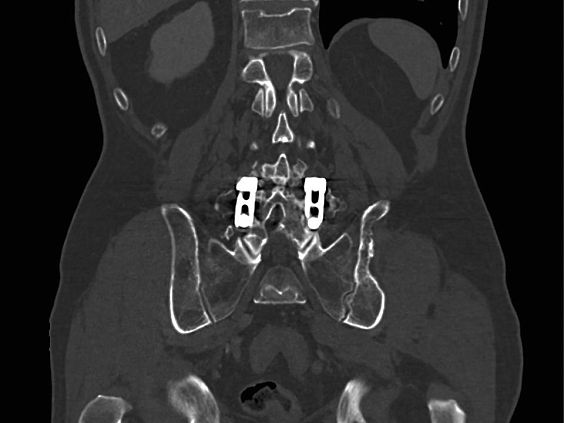

Клинические изображения

SOMATOM go.Up - компьютерный томограф для проведения рутинных и целевых осмотров, лучевой терапии и ангиографии. Система отличается инновационным дизайном рабочего места и полностью обновлённой концепцией сервиса, которая способствует снижению расходов по эксплуатации. Подходит для обследования головного мозга, легких, толстой кишки, сердца, сосудов. Вы можете заказать или купить со склада в наличии компьютерный томограф Siemens SOMATOM go.Up по выгодной цене, от надежного официального дистрибьютора "МСТ", с бесплатной доставкой в любой город по всей России.